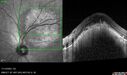

Central Retinal Vein Occlusion - Non-Ischemic - Excellent Outcome17 views57 year old man The right eye has had vision loss for about 3 weeks. He woke up with vision loss.

Medical Hx: HIV . Diabetes Mellitus (since 2014). Thyroid Disease.

Systemic Meds: gemboya. Metformin Hydrochloride. trulicity. losartan. vesepa. Synthroid .

VA OD: sc20/160 OS: sc20/20

TP: OD:14 OS:14

Treated with Avastin

VA 6 weeks later 20/32 – dry one shot.

Missed follow-up after second treatment and came 5 months later with good vision and no macular edemaAug 17, 2025